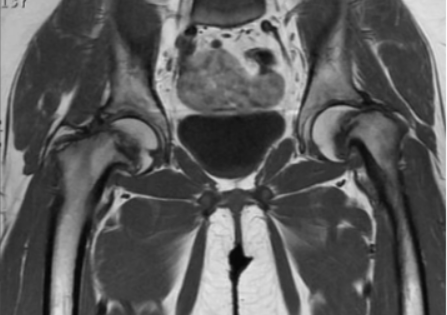

МР-скан коксофеморальных сочленений, вариант нормы

Интерпретацией изображений занимается врач-рентгенолог. В норме на серии томограмм травматических изменений не определяется:

структура костной ткани однородна, без дистрофических признаков;

субхондрального склероза суставных поверхностей нет;

капсула сочленений не утолщена, в полости присутствует небольшое количество синовиальной жидкости с однородным МР-сигналом;

костные крыши вертлужных впадин сформированы правильно, суставные щели равномерные, конгруэнтность (сопоставимость, согласованность) поверхностей сохранена;

целостность связочного аппарата не нарушена;

сигнал хрящевого компонента без особенностей, областей истончения нет;

краевые заострения суставных поверхностей вертлужных впадин отсутствуют;

окружающие мягкие ткани без видимой патологии;

бедренные и тазовые кости в зоне сканирования без очаговых изменений.